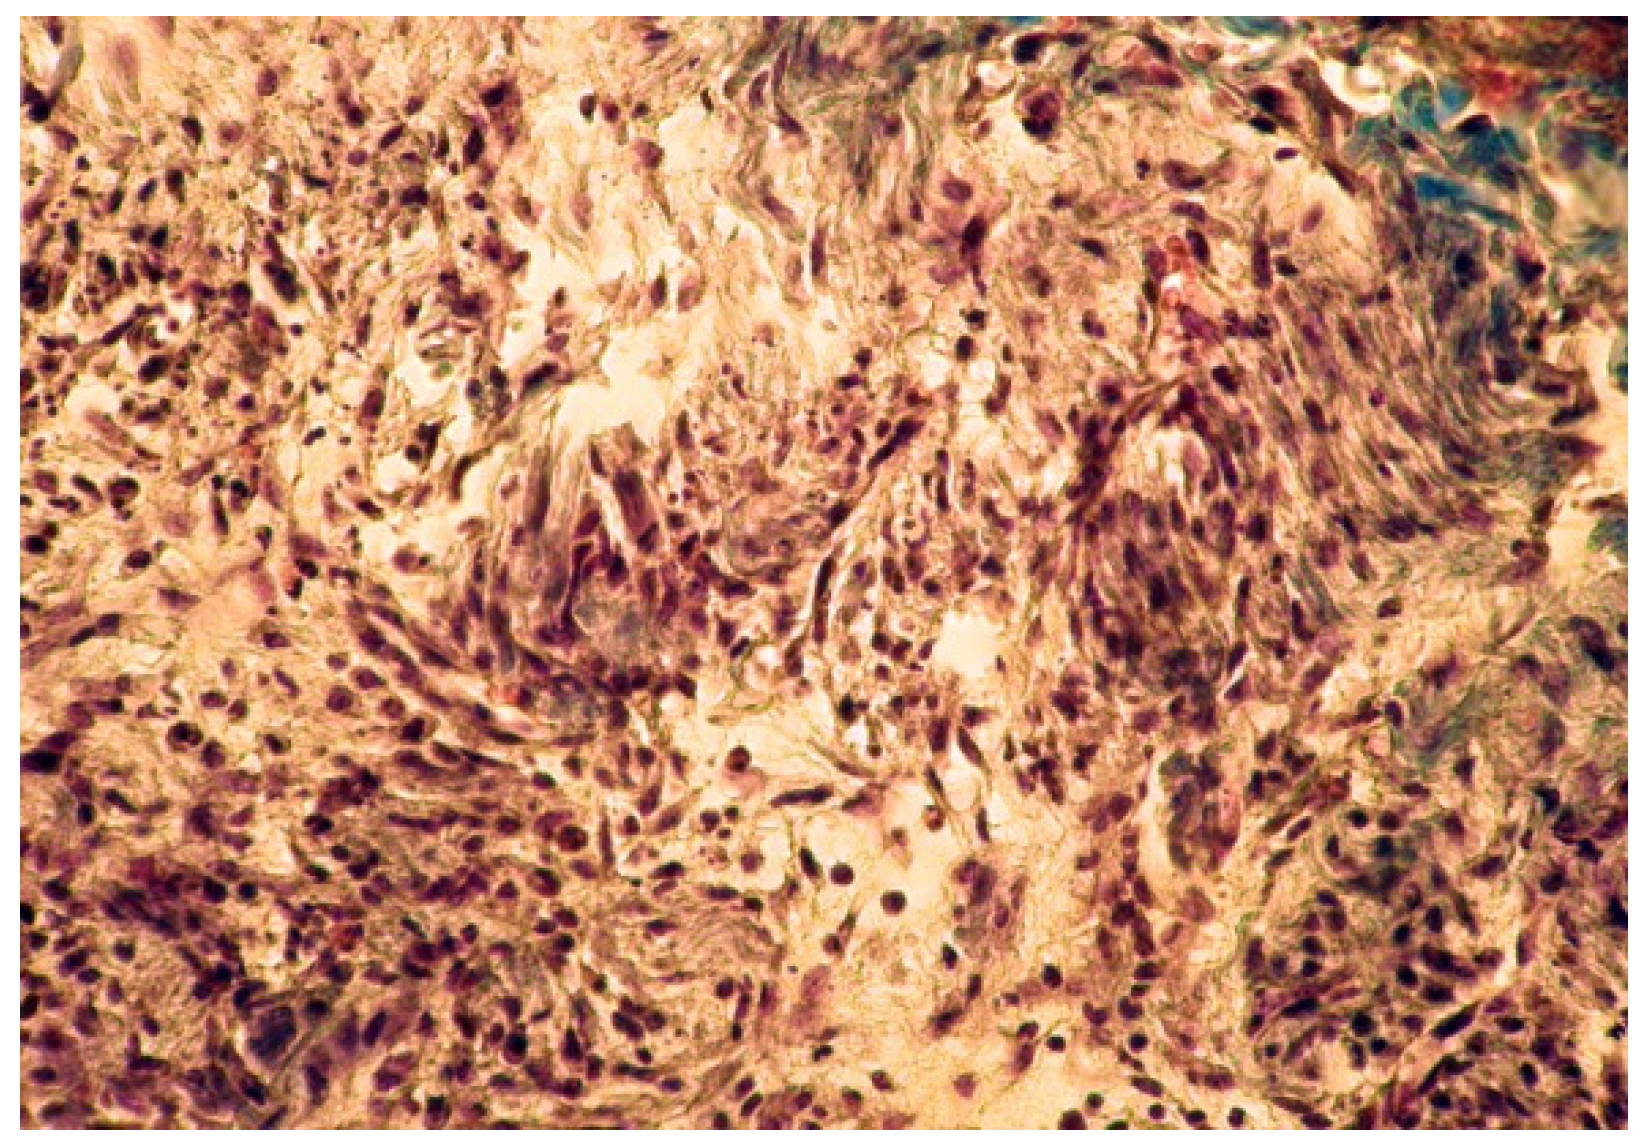

In group A (implanted with MTA) we noticed a well-defined area of peripheral necrosis (surrounding the biomaterial) in which incompletely resorbed MTA fragments and an intense influx of leukocytes consisting of macrophages, histiocytic cells, and neutrophils were present, together with a high number of fibroblasts and collagen fibers (Figure 4 and Figure 5).

Figure 4. Group A. Subcutaneous conjunctive tissue. Area of necrosis, intense leukocyte infiltration.

Figure 5. Group A. Buffer zone, consisting of fibroblast proliferation and collagen fiber synthesis. Col. Trichrome Masson, ×200.